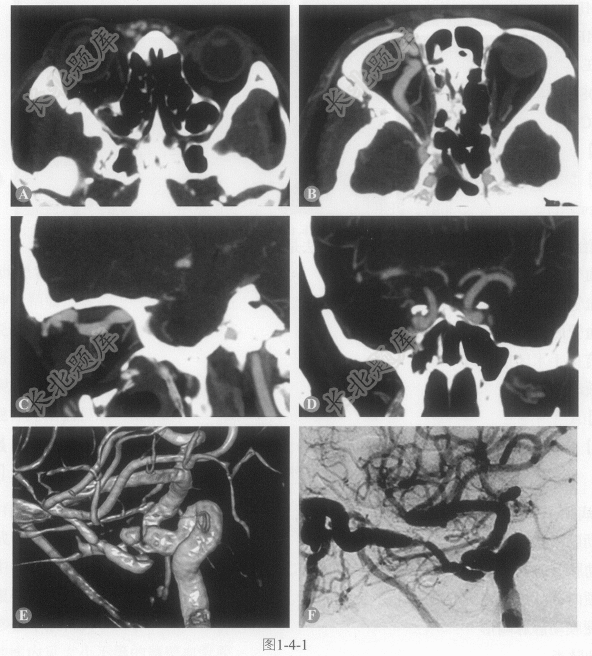

[材料题] 患者男性,36岁,右眼球突出、疼痛半月余,自觉视力轻度减退;曾有头部外伤史。右侧眼球突出,球结膜充血,眼球听诊可闻及搏动性杂音。

多项选择题1.此患者的CTA及DSA影像学(图1-4-1)表现包括:

A、右侧眼球突出

B、右侧海绵窦增宽

C、右侧眼上静脉曲张

D、右侧鼻部、颧颞部浅静脉曲张

E、CTA及DSA显示海绵窦与颈内动脉之间形成瘘口